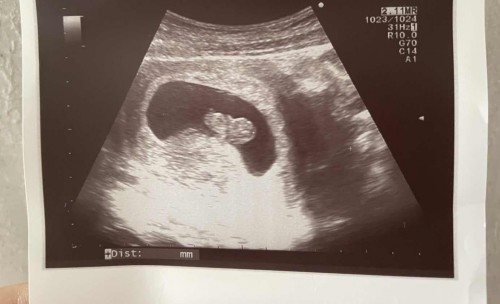

Week 9 ultrasound

Hi Mummies! Did my ultrasound today, do you think is a boy or girl? hehe #pregnancy #1stimemom